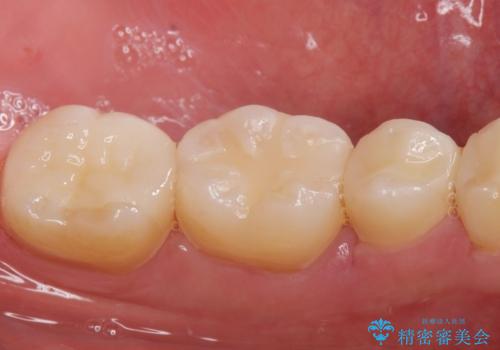

適合の良い詰め物が入りました。